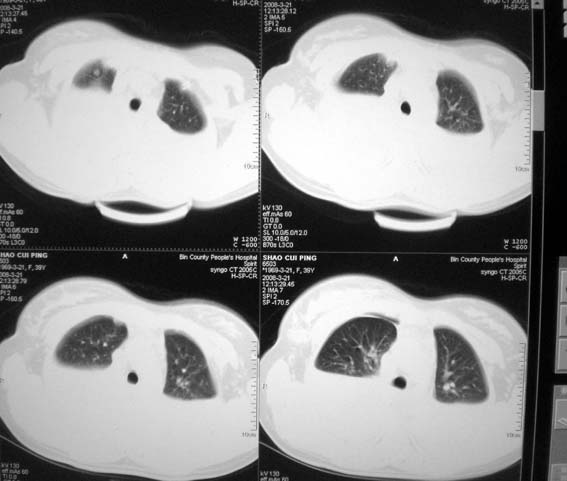

以下是引用zsl6918在2008-3-21 21:41:00的发言:[br]胸腔积液,心包积液,明确性质有难度。常规思路考虑结核性,建议抽液化验明确。

以下是引用卜一在2008-3-22 1:48:00的发言:[br][br] [br] 大量胸腔积液伴肺组织膨胀不全+心包积液。建议行纤支镜! [br] [br]

以下是引用随光逐影在2008-3-21 23:13:00的发言:[br]1)右肺中叶及左肺上叶舌段感染性病变。2)右肺中叶周围型肺癌待排。3)双侧胸腔积液并双下肺部分肺组织膨胀不全。4)心包积液。

以下是引用拾荒者在2008-3-22 21:21:00的发言:[br]胸腔积液、心包积液,双下肺膨胀不全,建议穿刺细胞学检查或抽液后进一步ct检查。